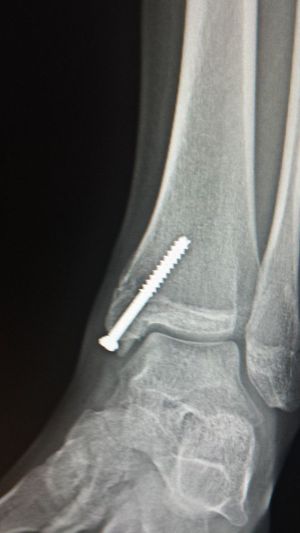

My ankle

Post surgery X-ray of my left ankle after breaking my medial malioulous

Surgery

Broken Bone